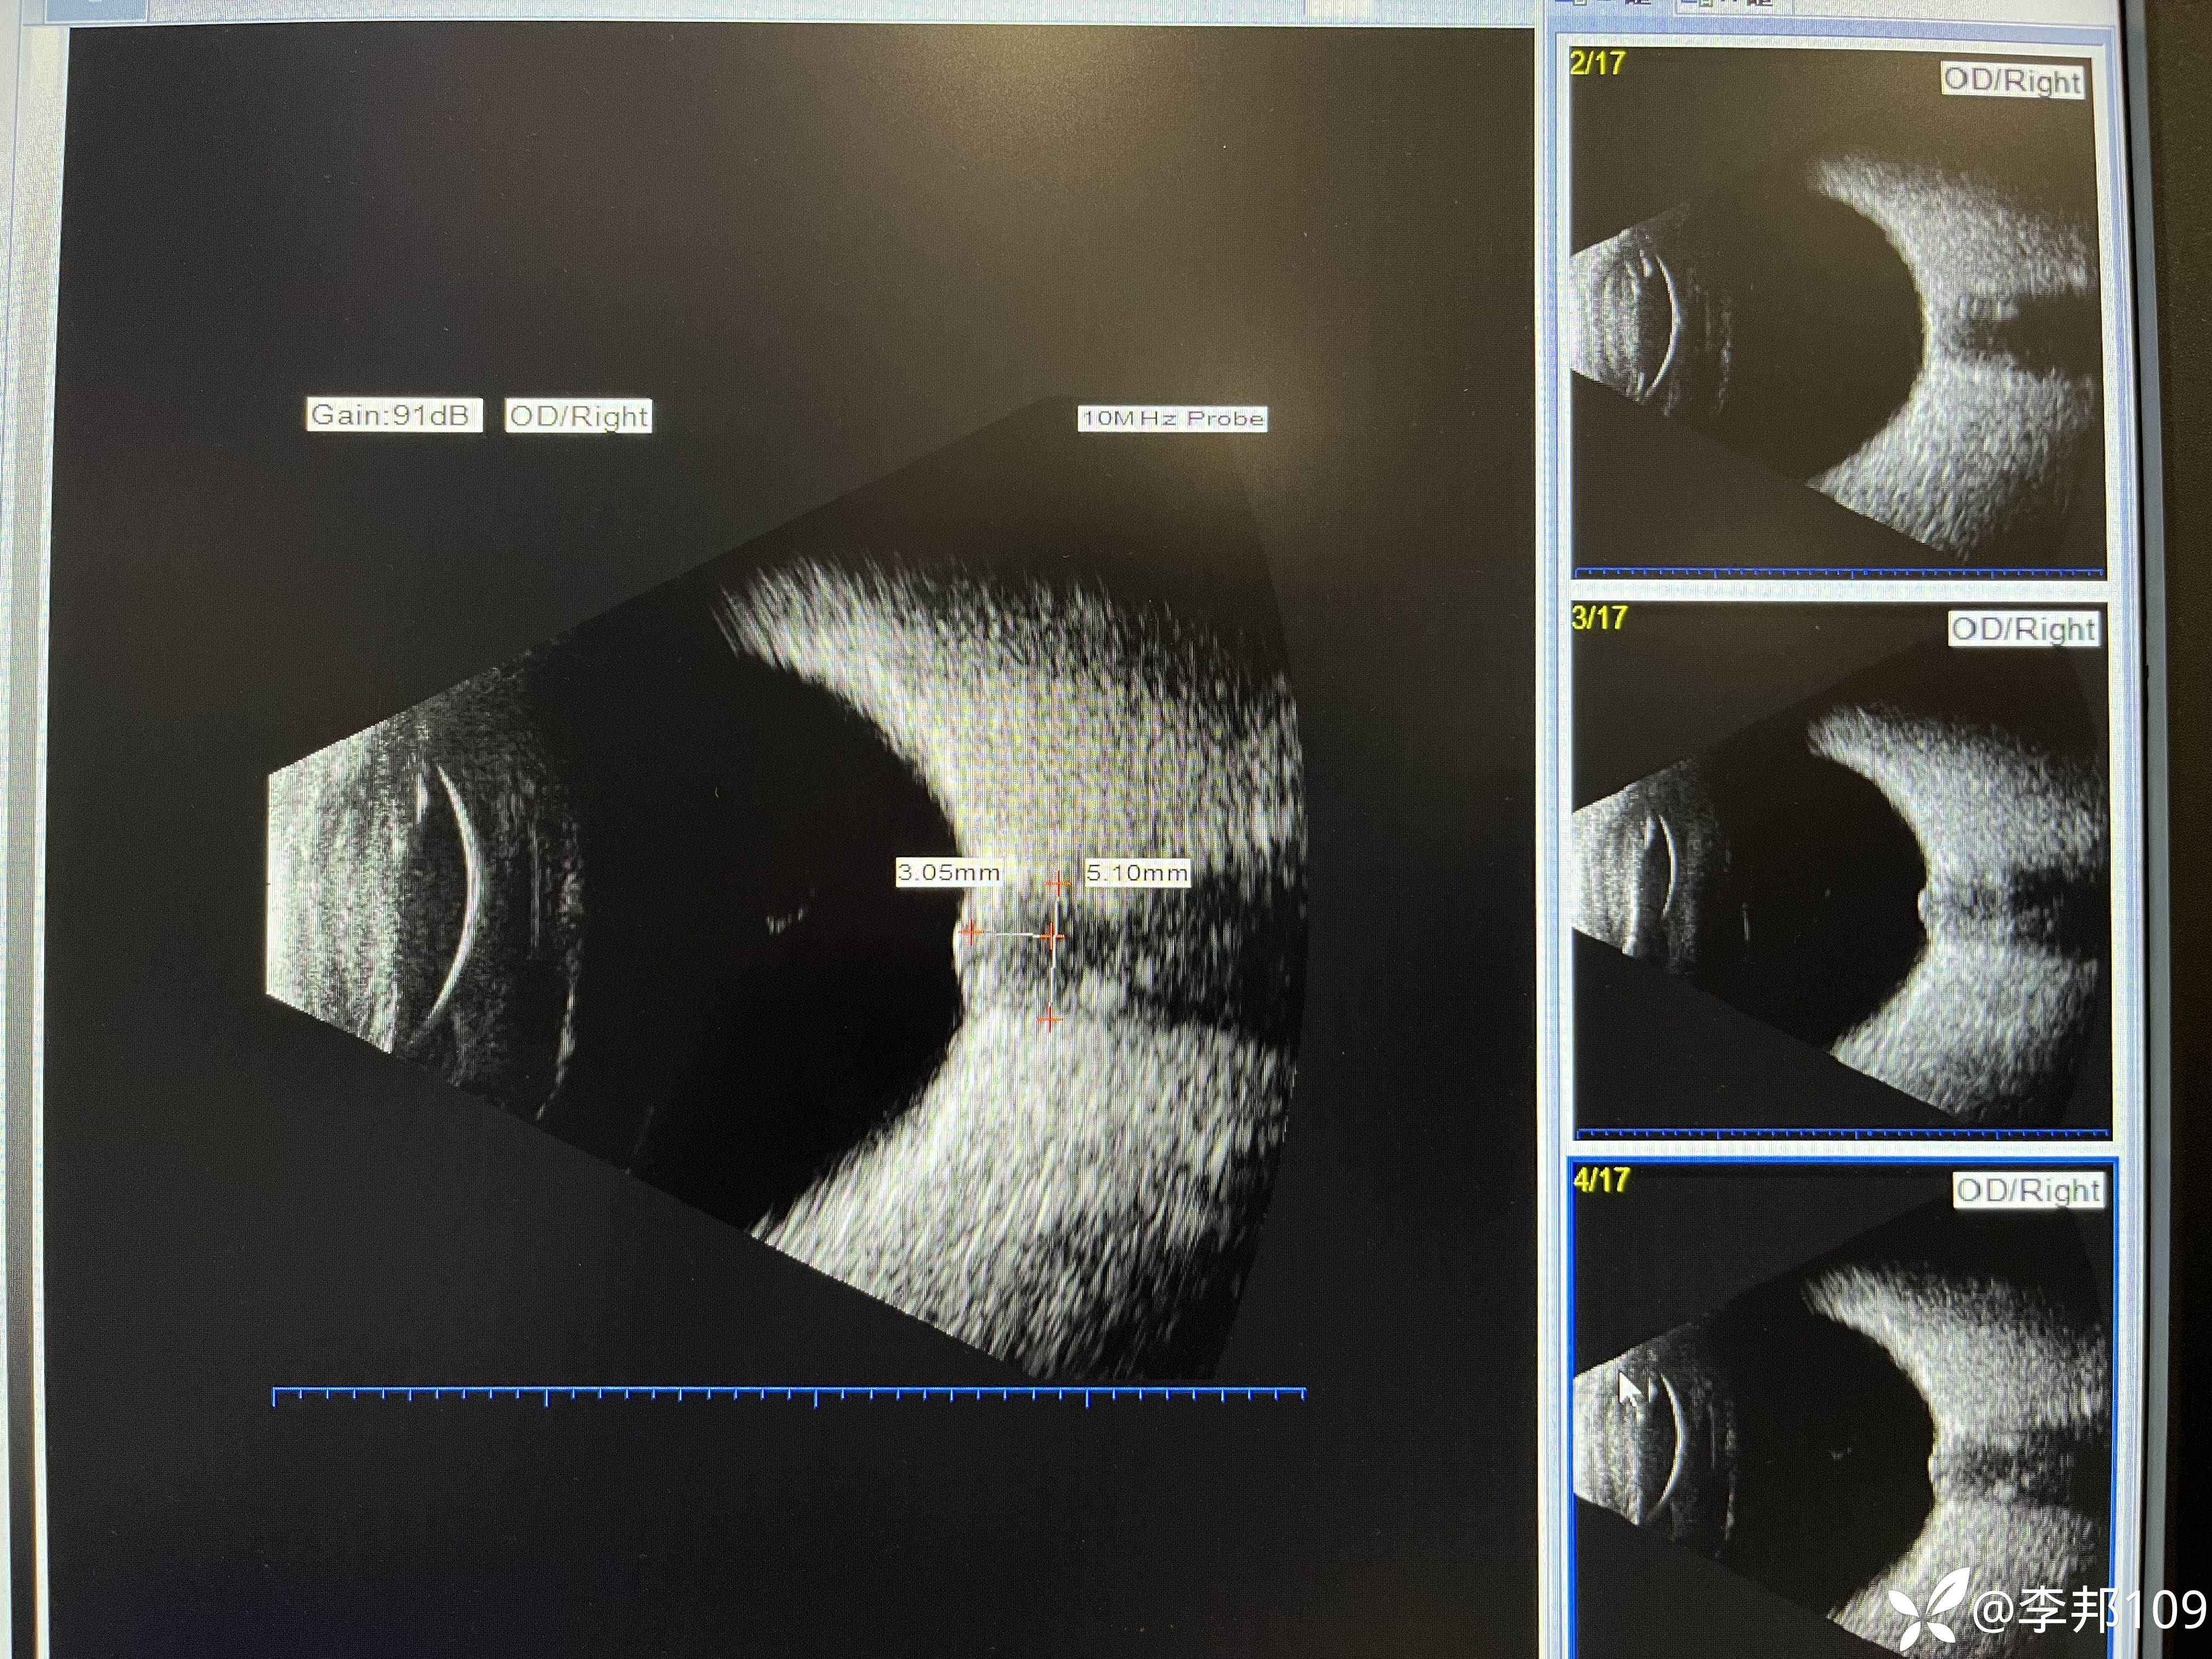

PHOMS引起视盘水肿及出血?

24岁,女,8百度近视,2百度散光。

诉求行近视手术摘镜

矫正视力双眼0.8-1.0。

没有感觉视力下降,无眼球转动痛,无色觉减退,瞳孔等大,无RAPD阳性。

询问既往病史无特殊。

只是近2月减肥20斤,近一周偶头晕,

但无头痛恶心呕吐症状。

行颅脑MRI未见明显异常。

没给安排做屈光手术,延期进行。

建议神经内科,患者没去,观察中

之前见过的肥胖者发生特发性颅内高压引起视盘水肿,但是水肿的比这个严重

这个患者不胖,视盘水肿也不重,视力下降也不明显。

如何查因呢……